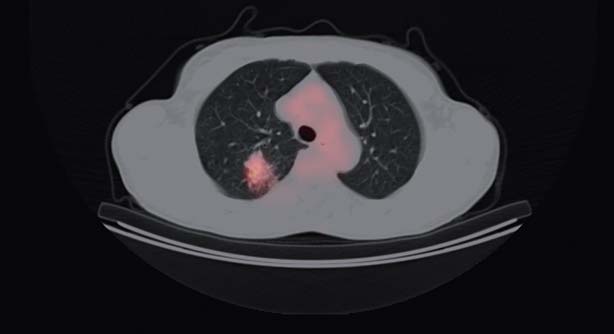

Obraz PET/CT klatki piersiowej w przekroju poprzecznym. Widoczny ogniskowy wychwyt radioizotopu w płucu prawym